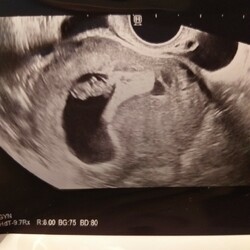

You are not alone 💞 ! Ik ben 42 en onverwacht zwanger van mijn derde, na 2 dochters (oudste 20, jongste bijna 10 maanden. De jongste was ondanks mijn leeftijd zeker gepland ivm jarenlange wens voor een tweede. Extra controles laten doen en pretecho's tussendoor, evenals nipt test. Laatste maanden zwangerschap waren pittig door veel maagklachten ,vocht en beknelde zenuw in mijn lies .Ingeleid met 38 weken helaas heftige bevalling met een weenstorm en veel bloedverlies. Daarom moet ik de huidige zwangerschap echt nog even op me in laten werken, ben eerlijk gezegd toch nog flink in shock. Maar zoals ze zeggen, geen 1 zwangerschap is hetzelfde dus kan net zoals bij de eerste ook vlekkeloos gaan.

Hier ook 40 Jr toen ik zwanger werd van mijn eerste. Nu net 43 geworden en bewust zwanger van de tweede! Ja ik vind het ook erg spannend. Mijn vorige zwangerschap werd medisch omdat mijn zoontje niet snel genoeg groeide in mijn buik. Uiteindelijk met 39w1d ingeleid. Erg spannend vond ik dat. Het is gelukkig goed gegaan en ik ben binnen 8 uur bevallen van een klein maar gezond kereltje ❤ Die ervaring speelt nu toch ook mee. Destijds heel veel extra echo's gehad en behoorlijk veel stress ervaren. Ik hoop dat dit kindje groter zal zijn! Maar ik voel nu wel meer vertrouwen tov de bevalling. Dat is fijn :)